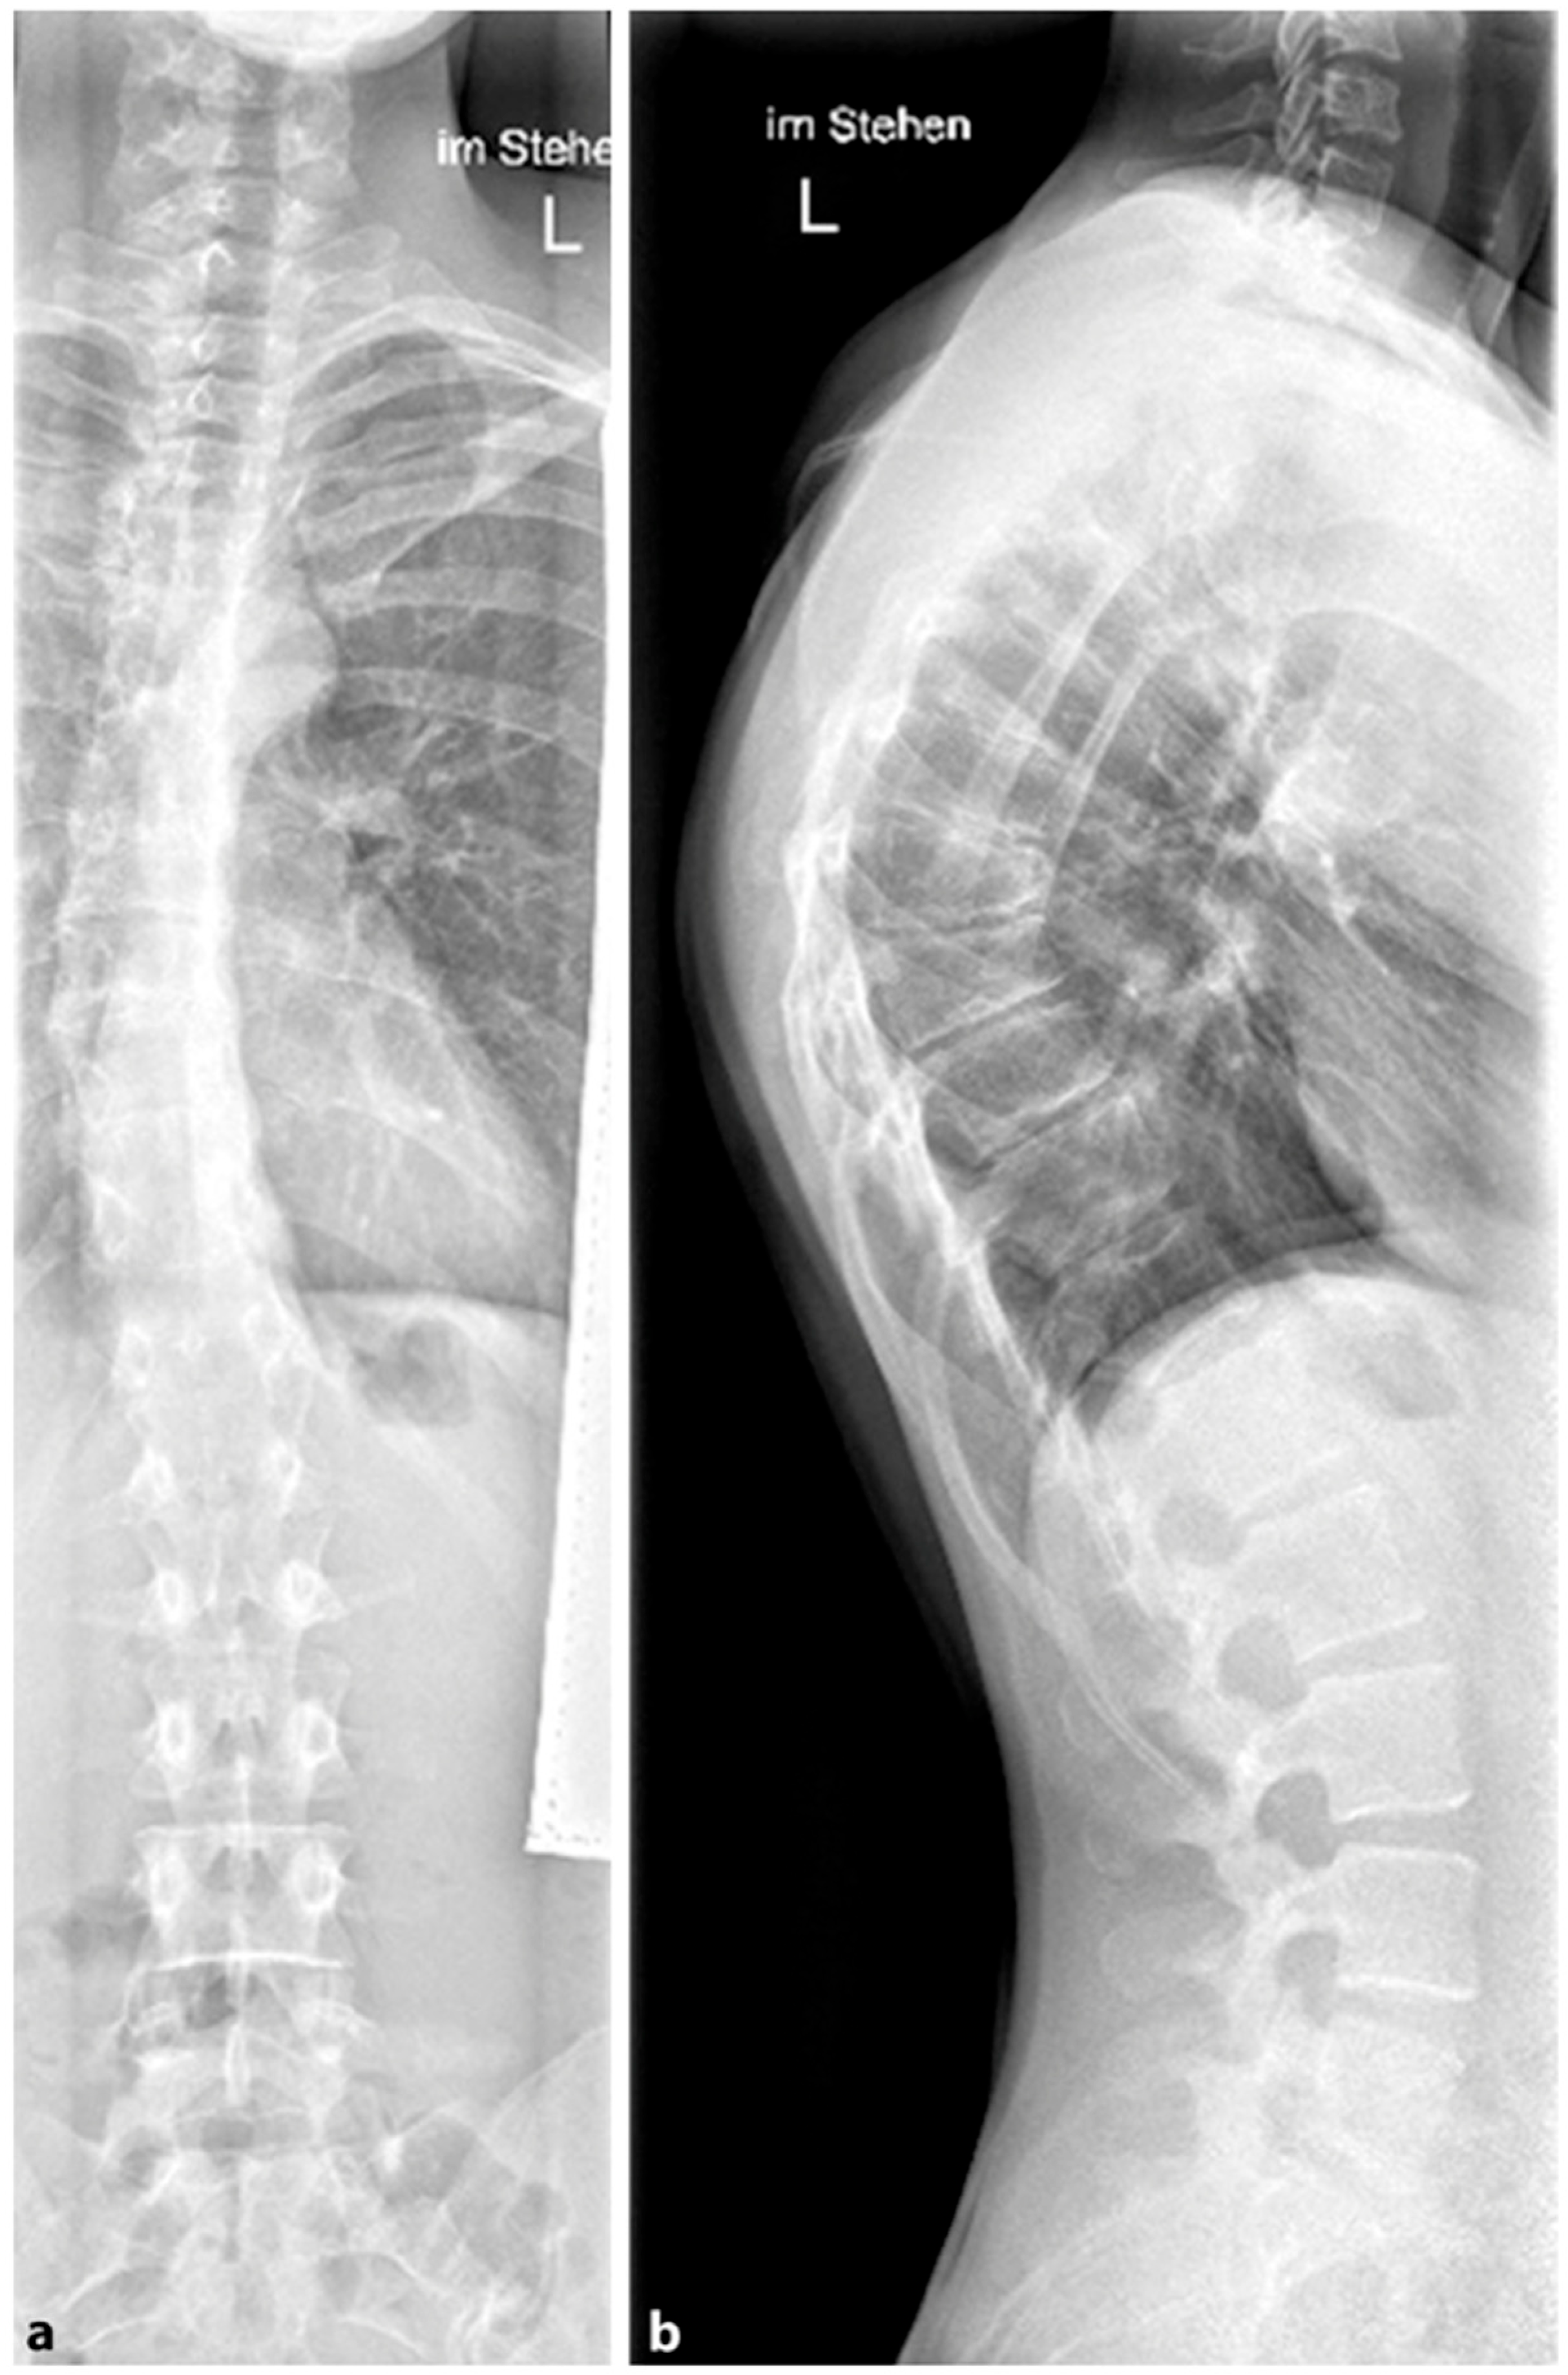

4.2. Diagnostics

Although initially described by Sorensen, the definition of SD has been definitively established by subsequent work by Edgren et al. and Blumenthal et al., with SD typically manifesting mostly in the thoracic spine (type I) and less commonly in the lumbar spine (type II) [79,85,86]; see Figure 7. The measurement of thoracic kyphosis according to Cobb (Th1–Th12) is sometimes difficult on conventional X-rays due to the humeral heads, so the Stagnara angle (Th4–Th12) is a reliable alternative (Figure 8). In children with SD, back pain and a positive family history are common, and clinical examination typically reveals a gibbus and a flexible deformity. In addition to a detailed medical history, a thorough physical examination is of utmost importance. The various signs and findings typical of SD are listed in Table 2.

4.2.1. X-ray

A standing anterior–posterior and lateral spinal radiograph is part of the standard imaging. Stereoradiographic imaging can be used alternatively to conventional radiography to create a three-dimensional reconstruction of a biplanar spinal X-ray with significantly less radiation exposure (EOS™) [31]. In addition to the representation of the kyphosis in the lateral view, these images also show the extent of curvature in the frontal plane according to Cobb, the curvature pattern, the sagittal profile or sagittal balance, and the apical vertebra. An assessment of spinal flexibility can be made using a clinical examination or a hyperextension lateral radiograph. The various features can be observed in radiological diagnostics, as shown in Figure 7. In up to 50% of cases, scoliosis and spondylolysis are accompanying pathologies [87,88].

Figure 3. Patient post-Harrington instrumentation from T4 to L1 performed in 1980 (reprinted with permission [10]).